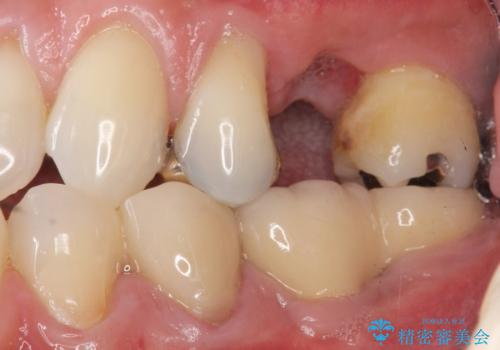

- 奥歯のかぶせ物が土台ごとはずれてしまったことを主訴に来院された患者様です。

残根状態になっている左上の小臼歯(左上5)を精査したところ、う蝕が歯肉縁下まで進行しており保存不可能な状態でした。

患者様のご希望により、抜歯後インプラント治療を行いました。

骨の厚みが不足していたため、インプラントの埋入と同時にソケットリフト(上顎骨に骨を増やす手術)を行いました。